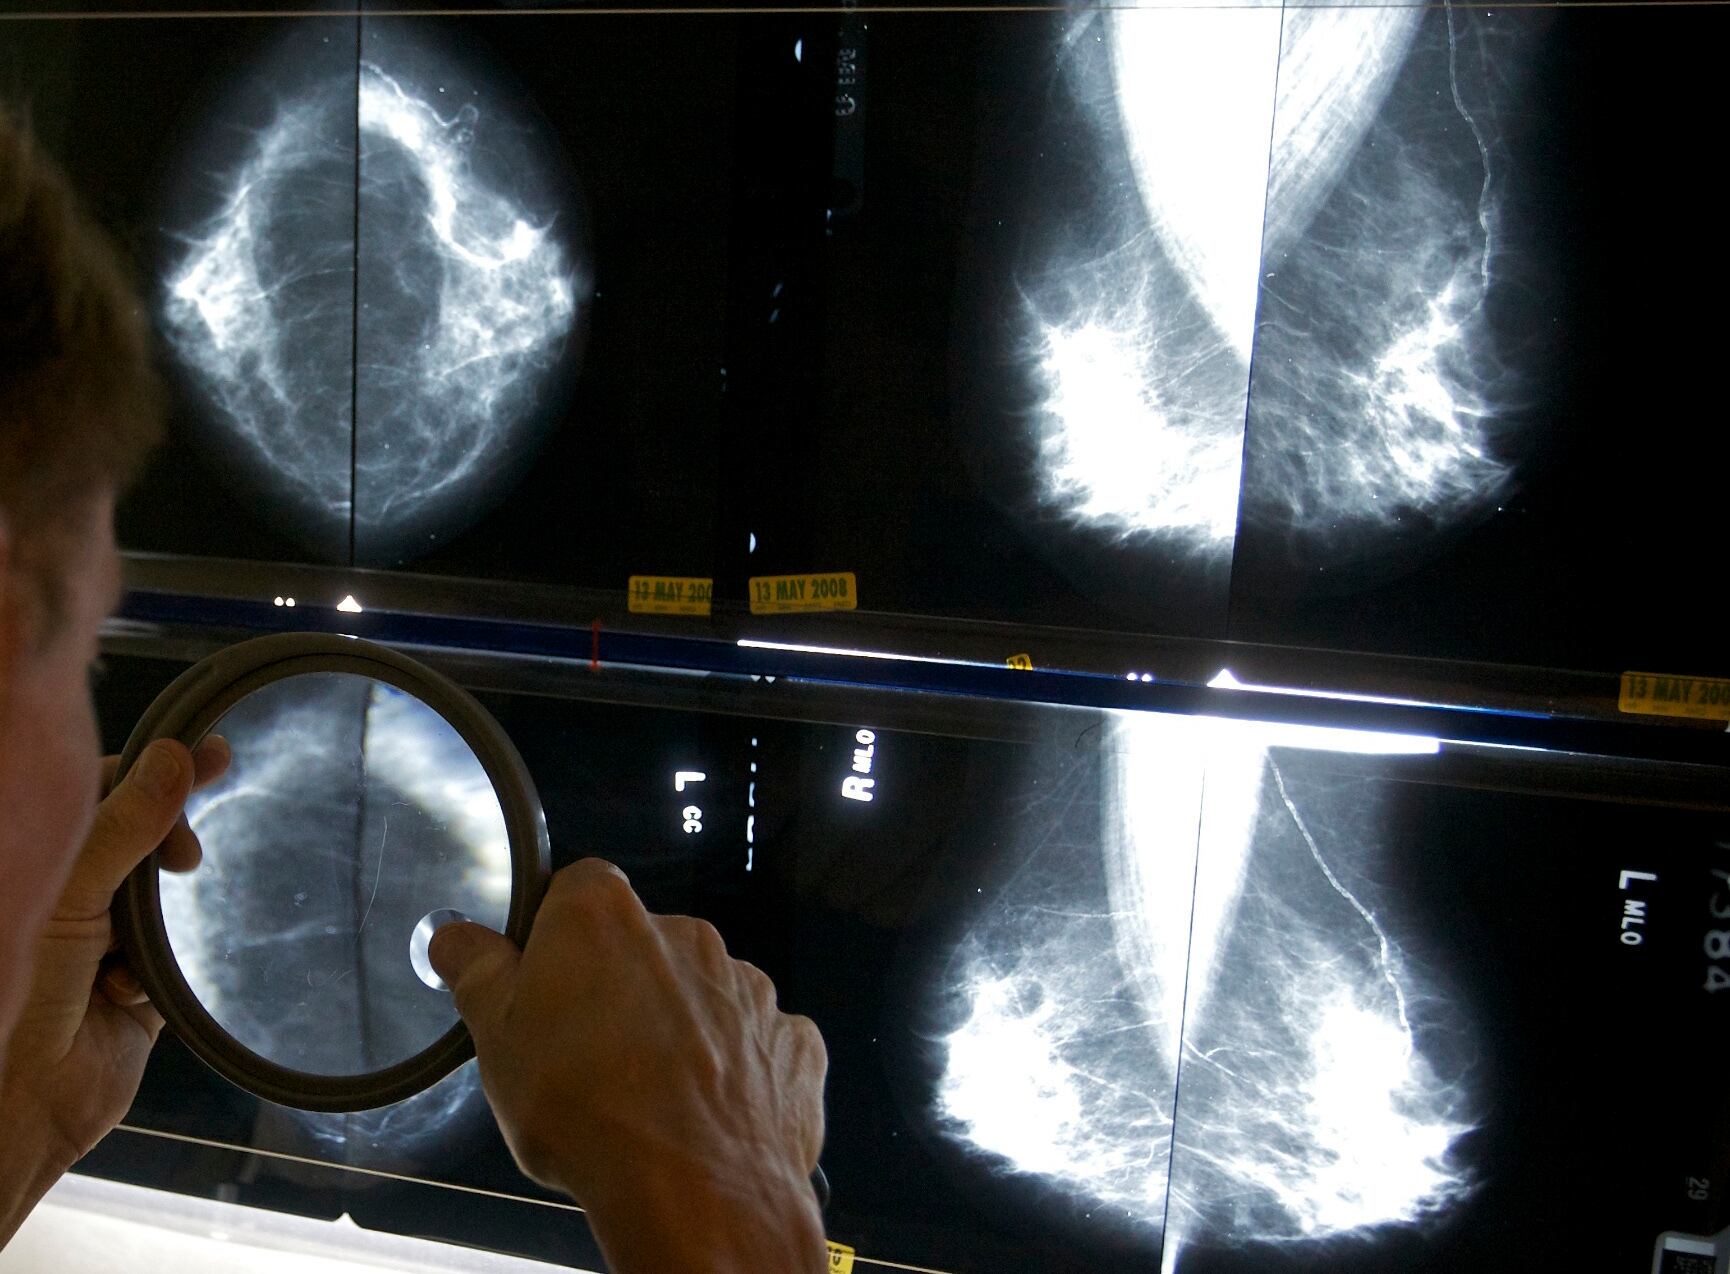

Aproximadamente la mitad de las mujeres mayores de 40 años tienen mamas densas, con menos tejido adiposo y más tejido conjuntivo y glandular. Ese tejido aparece blanco en las radiografías, del mismo color que los tumores mamarios, lo que dificulta la lectura de las mastografías. El tejido mamario denso es uno de los factores que puede aumentar las probabilidades de que una mujer desarrolle cáncer.

Según las nuevas normas, las mujeres con mamas densas recibirán una nota escrita alertándolas de que su estado “dificulta la detección del cáncer de mama”. También se les indicará a esas pacientes que hablen con su médico sobre los resultados.